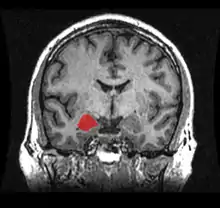

Dorsal view of the amygdalae in an average human brain Frontal view of the amygdalae in an average human brain

Left lateral view of the amygdala in an average human brain Amygdala highlighted in green on coronal T1 MRI images